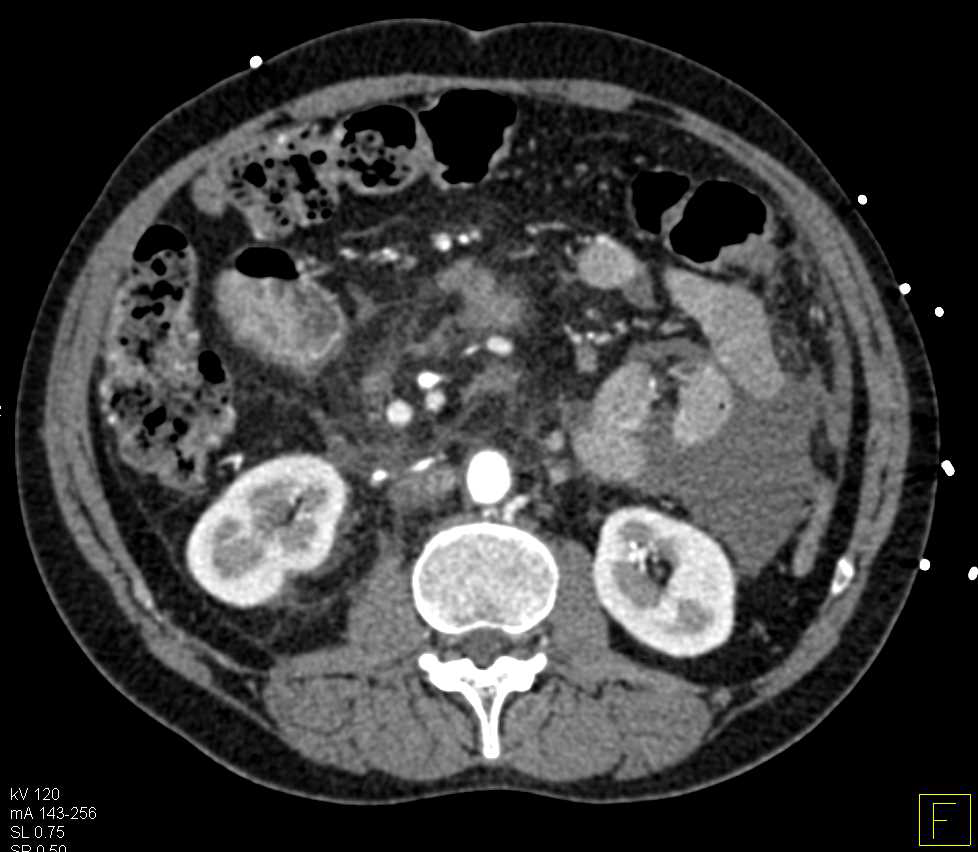

Hepatocellular Carcinoma (Hepatoma) with Bilateral Adrenal Metastases